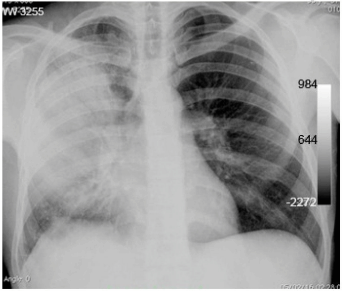

Paciente do sexo masculino, 35 anos, chegou ao pronto-socorro com febre alta há cinco dias, expectoração e tosse produtiva. O médico que o atendeu, após o exame clínico, solicitou uma radiografia de tórax (abaixo).

A partir dos dados apresentados, assinale a alternativa que representa o achado radiológico.